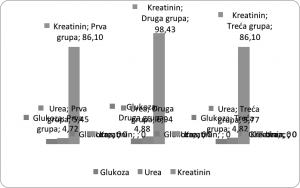

Poslije analize dobivenih rezultata, utvrđene su sljedeće vrijednosti. Utvrđeno da se ispitivani pacijenti mogu razvrstati u tri dobne skupine: starost od 30 – 40 godina (prva grupa), 40 do 50 godina (druga grupa) i 50 – 60 godina (treća grupa). Broj pacijenata starosne dobi 30 – 40 godina je 18, a po 21 pacijent je u skupinama pacijenata starosne dobi od 40 – 50 i 50 – 60 godina. Nakon izračunavanja srednjih vrijednosti biohemijskih parametara po dobnim skupinama kod pacijenata sa normalnim vrijednostima koncentracije glukoze u krvi, podaci su prikazani i grafički (Grafikon 1.)

Grafikon 1. Promjena vrijednosti koncentracije glukoze, ureje i kretinina u odnosu na starosnu dob – skupina pacijenata sa normalnim vrijednostima glukoze u krvi

Kao što se može uočiti iz grafikona, koncentracije glukoze, ureje i kreatinina su najviše kod dobne grupe pacijenata od 40 – 50 godina. Najniže vrijednosti su uočene kod pacijenata prve grupe (30 – 40 godina). Povećanje ili smanjenje koncentracije glukoze prati povećanje ili smanjenje koncentracije kreatinina i ureje. Iz Tabele 5. se može uočiti da su vrijednosti ureje i kreatinina uglavnom u referentnim granicama kod pacijenata sa normalnom koncentracijom glukoze u krvi. Međutim, povećana koncentracija ureje je prisutna kod dva pacijenta iz prve grupe; jednog pacijenta iz druge grupe, dok kod pacijenata iz treće grupe nema odstupanja od referentnih vrijednosti. Što se tiče kreatinina, tri pacijenta iz prve grupe imaju vrijednost kreatinina van referentnih granica, kod druge grupe ni jedan pacijent nema povećanu vrijednost kreatinina, kao ni kod treće grupe. Nakon izračunavanja srednjih vrijednosti biohemijskih parametara po dobnim skupinama kod pacijenata sa povećanim vrijednostima koncentracije glukoze u krvi iz Tabele 5., podaci su prikazani i grafički (Grafikon 2.)

Grafikon 2. Promjena vrijednosti koncentracije glukoze, ureje i kretinina u odnosu na starosnu dob – skupina pacijenata sa povećanim vrijednostima glukoze u krvi

Kod skupine pacijenata sa povećanom koncentracijom glukoze u krvi, uočava se povećanje koncentracije glukoze, ureje i kreatinina sa povećanjem starosne dobi pacijenta. Tako su najniže vrijednosti zabilježene kod prve grupe, a najviše vrijednosti kod treće starosne grupe pacijenata. Također, povećanje ili smanjenje koncentracije glukoze prati povećanje ili smanjenje koncentracije kreatinina i ureje. Urea i kreatinin su u referentim granicama ili povećanim koncentracijama. Povećana koncentracija ureje je prisutna kod jednog pacijenta iz prve grupe; pet pacijenta iz druge grupe, kao i pet pacijenata iz treće starosne grupe. Što se tiče kreatinina, jedan pacijent iz prve grupe ima vrijednost kreatinina van referentnih granica, kod druge grupe 5 pacijenata ima povećane vrijednosti, dok kod treće grupe tri pacijenta imaju povećane vrijednosti. Kod skupine pacijenata sa povećanom koncentracijom glukoze, ovo odstupanje od referentne vrijednosti se može povezati sa nefropatijom kod dijabetičara. Za nastanak morfoloških promjena bubrega odgovorni su brojni metabolički činioci i procesi, kao što su: hiperglikemija i neenzimatska glikolizacija (promjene bazalne membrane i drugih struktura glomerula), biohemijske promjene u ekstraćelijskom matriksu (smanjena sinteza najvažnijeg glikozoaminoglikana heparin-sulfata, kao i sinteza sijalične kiseline – sijaloglikoprotein, povećana biosinteza kolagena, glavnog sastojka ekstraćelijskog matriksa), gubitak negativnog naelektrisanja glomerulske bazalne membrane, povećani intraglomerulski pritisak, kao i fizička sila, može da ošteti površinu endotela i epitela, kao i normalnu funkciju glomerulske barijere. Najranija promjena u funkciji bubrega kod dijabetesne nefropatije glomerulska hiperfiltracija i hipertenzija, za šta su odgovorni hemodinamski i humoralni činioci: hiperperfuzija bubrega (povećanje filtracionog pritiska, povećan otpor u aferentnoj i eferentnoj arterioli, posebno u eferentnoj, povećanje glomerulskog transkapilarnog hidrauličnog pritiska, povećanje kapilarne površine – povećanje ultrafiltracionog koeficijenta, hiperglikemija). Posljedica nefropatije se vide i u krvnoj slici: vrijednosti kreatinina je povećana. Kod skupine pacijenata sa normalnim vrijednostima glukoze u krvi, povišene individualne vrijednosti kreatinina i ureje se mogu povezati sa nekim drugim oboljenjima. Na primjer, povišena koncentracija ureje u serumu je kod bolesnika koji imaju smanjenu funkcionalnu sposobnost bubrega (glomerulonefritis, pijelonefritis, nefroskleroza) i kod bolesnika kod kojih je povećana razgradnja proteina u organizmu (groznica, nekroza) i povrede. Povećane vrijednosti kreatinina nalazimo kod akutne i hronične bolesti bubrega ili opstrukcije mokraćnog sistema.